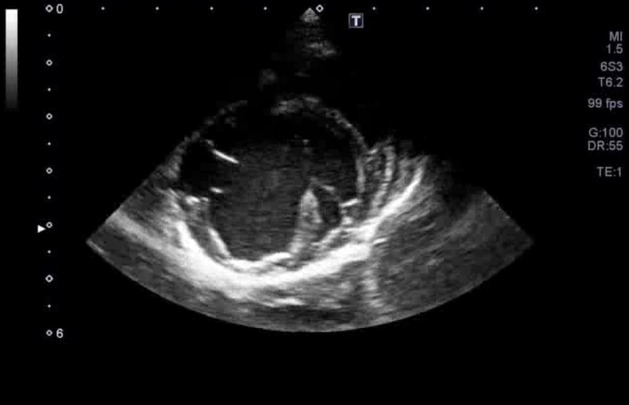

図3C 心原性肺水腫の猫における肺超音波画像

雑種猫、8歳5カ月齢、去勢雄、体重4.68kg。心疾患の管理中であったが、3日ほど投薬できておらず、かかりつけ医より紹介来院した。肺水腫によりB-lineの増加(white lung)が認められた。

特集 悩ましい猫の肺炎 vs. 肺水腫 vs. 肺腫瘍(塗木貴臣先生)図3Ⅽ